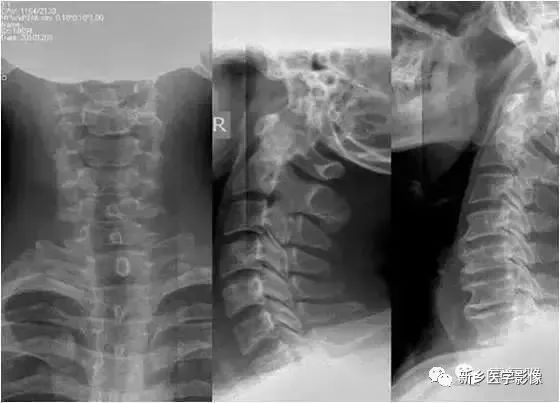

颈椎正位

颈椎正位片的临床意义在于:

1、从正位方向观察颈椎排列情况和曲度的改变;

2、观察构锥关节的结构和增生情况,从而推断椎动脉型颈椎病的发生和程度。

3、观察双侧椎弓根和棘突(都是轴位显示)之间的关系;

4、左右颈部软组织内的异常密度情况。

颈椎侧位

颈椎斜位

拍颈椎双斜位片,主要用来观察椎孔的大小和钩椎关节的骨质增生情况。钩椎关节增生以后,使椎间孔变小,在颈椎斜位片能显示出来,它是产生神经根刺激及椎动脉供血不全的原因。

但是,临床上有些骨质增生明显,并占据椎间孔横径的2/3者也无任何症状。